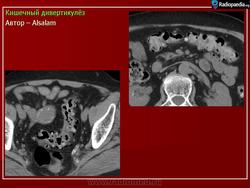

Кишечный дивертикулёз. Пнд, 09/09/2013 - 22:01 #1 Катенёв Валенти... Не на сайте Был на сайте: 7 лет 5 месяцев назад Зарегистрирован: 22.03.2008 - 22:15 Публикации: 54876 Дивертикулёз сигмы и нисходящей ободочной кишки Fig.23.: Radiographic image: multiple, round filling defects are seen on the sigma and on the descending colon. Втр, 11/11/2014 - 13:06 #2 Катенёв Валенти... Не на сайте Был на сайте: 7 лет 5 месяцев назад Зарегистрирован: 22.03.2008 - 22:15 Публикации: 54876 Продолжение. Приложения:

Продолжение.